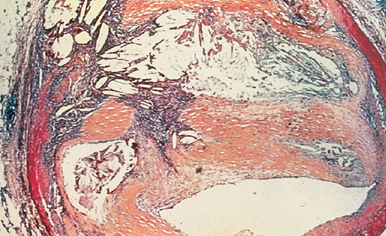

coronary artery section in pt with familial hypercholesterolemia. what’s in it?

platelets and RBCs + fibrin = thrombus (at an early age)